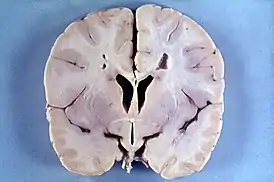

Болезнь Александера — патологоанатомически демиелинизирующая лейкодистрофия — заболевание, проявляющееся в раннем детском возрасте (до года), является наследственным. Аутосомно-доминантный тип передачи. Свойственны нарушения метаболизма в астроцитах. Наблюдается задержка умственного развития, увеличение массы головного мозга, высокая температура, судорожные припадки, слабый мышечный тонус, прогрессирующая гидроцефалия, пирамидные знаки. У детей Болезнь Александера протекает катастрофически, иногда наступает смертельный исход при проявлениях спастической тетраплегии и децеребрационной ригидности. У взрослых более медленное течение заболевания, с ремиссиями и остановками. Прогрессирует заболевание быстро, рано наступает летальный исход.

При магнитно-резонансной томографии головного мозга (МРТ) при болезни Александера выявляется демиелинизация различных отделов мозга (при инфантильной и юношеской формах — преимущественно в лобных с распространением на другие области, при взрослой — более выражена в мозжечке и стволе мозга).

Подтверждением заболевания служит обнаружение волокон Розенталя (что возможно при биопсии мозга или уже после смерти при вскрытии).